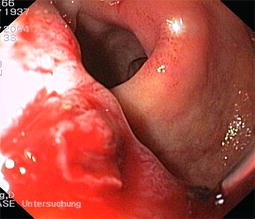

Abb. 1